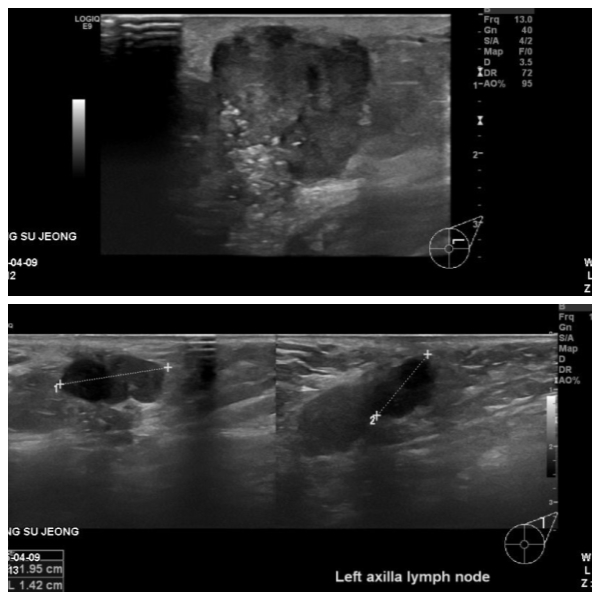

좌측유방에 만져지는 멍우리로 내원하신 60대 환자분이십니다.

본원에서 시행한 초음파상 우측유방 상외측에 혹과 겨드랑이에 임파선이 부어있었고

각각 조직검사와 세침검사 시행하여 결과상

침윤성유관암 겨드랑이전이로 진단되었습니다.